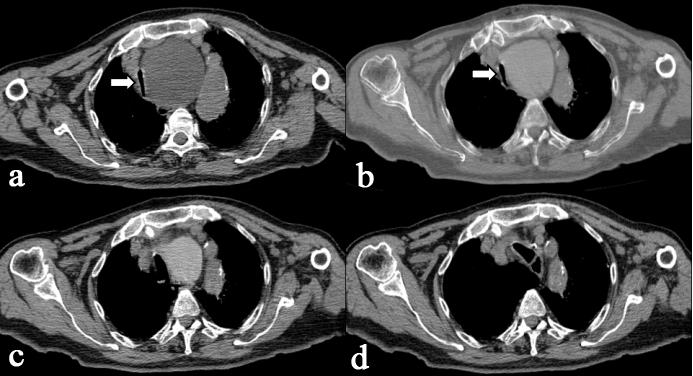

11月3日,患者坐轮椅进入了CT介入手术室,在介入医学中心主任徐晓雪教授的指导下,由介入医学中心副主任李兵副主任医师、余枭漩医师进行手术。在CT精确引导下,穿刺至囊肿内,并放置引流管,引流囊液,随着囊液的引出,患者明显感受到呼吸困难逐步缓解。为了防止囊肿复发,在囊液完全引出后进行了囊肿硬化治疗。术后CT复查显示患者受压气管复位、狭窄解除,管腔宽度恢复。手术全程仅用40分钟,使用局部麻醉,患者生命体征全程监控,手术过程中老人家意识清醒、生命体征平稳。近日老人已顺利出院,呼吸困难及吞咽困难明显缓解,生活质量显著提高,老人家及家属对治疗效果极为满意。

(术中CT扫描:图a、b、c、d显示不同时间相同层面囊肿情况,可见囊肿逐步缩小,主支气管逐步复位、直径增宽。囊肿内高密度为注入的造影剂。)